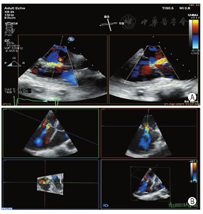

患者男,87岁,心房颤动10余年,近1年胸闷、憋喘、伴下肢水肿,不能平卧。术前经胸超声心动图(TTE)及经食管超声心动图(TEE)示:①下腔静脉宽19 mm(无呼吸塌陷率)、双房及右室增大伴轻度二尖瓣反流及极重度三尖瓣反流(tricuspid regurgitation,TR);②轻度主动脉瓣反流;③中度肺动脉高压(57 mmHg)(1 mmHg=0.133 kPa);④左室收缩功能未见异常(LVEF:63%)(图1,图2)。心电图示:心房颤动,频发室性期前收缩,ST-T改变;胸部X线示:双肺渗出,肺气肿、肺大泡,右侧胸水。CT示:三尖瓣瓣环扩大(直径:58.2 mm),右房增大(最长径:92.4 mm),下腔静脉开口增宽。临床诊断:①极重度三尖瓣关闭不全,NYHA心功能Ⅲ级;②心房颤动。鉴于该患者年龄较大以及肺气肿合并肺大泡,外科手术高危(STS评分8分,EuroscoreⅡ评分7分)症状性极重度TR,介入医生决定行经导管三尖瓣修复术。

该例患者为继发于心房颤动的FTR,三尖瓣瓣环显著扩及减少TR的作用,2D、3DTEE在评估FTR患者瓣环形态、大小、反流颈形态部位以及K-Clip™术中引导和评价中具有重要作用。